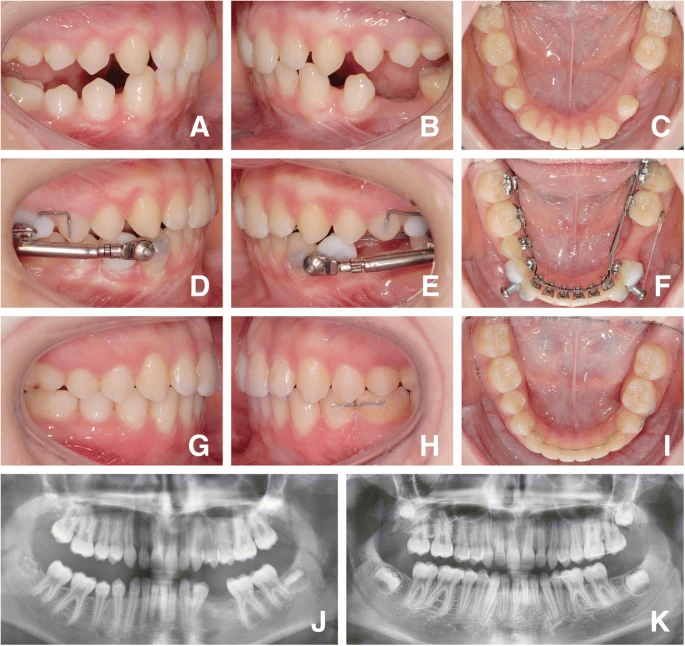

Kawat gigi (behel)

Pada keadaan tertentu, kehilangan gigi dapat diatasi dengan penggunaan behel. Spesifiknya, pada gigi geraham dimana gigi yang bersisa dibelakangnya ditarik ke area gigi yang sudah hilang